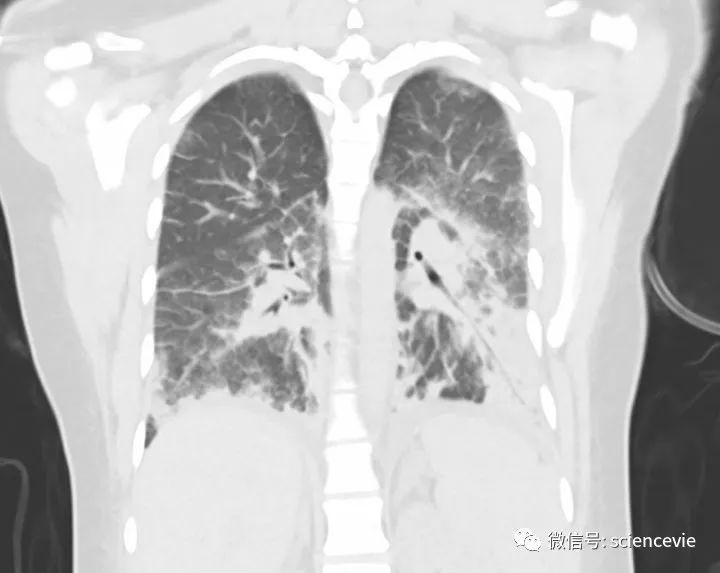

该扫描影像呈现了一名吸食四氢大麻酚的 19 岁女性的肺损伤。